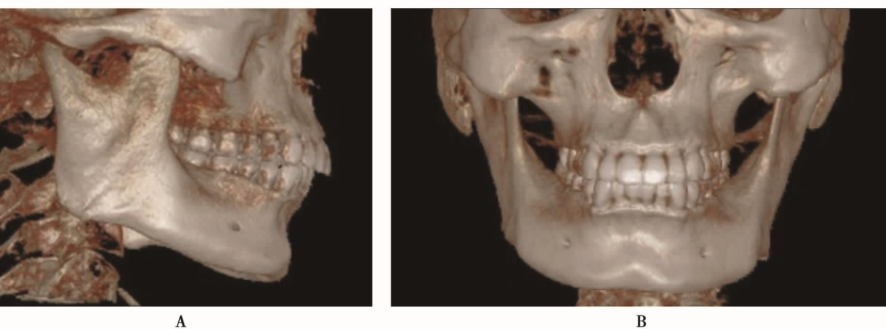

下颌支由喙突、髁突、内、外面四部分组成。下颌骨牙槽突的内侧骨板和外侧骨板都由骨密质构成,骨松质被内外侧骨板包绕其中(图1~3)。

图2 CBCT三维重建图示下颌骨呈蹄铁形,由下颌体和下颌支组成A.侧位图像;B.正位图像